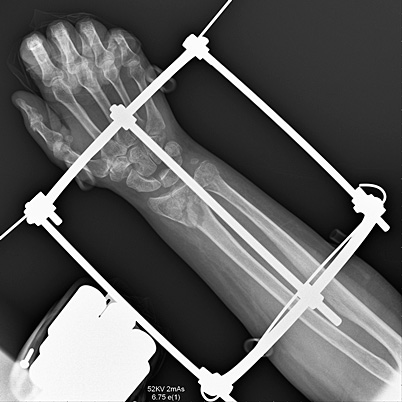

При поступлении выполнена экстренная операция – фиксация перелома в аппарате внешней фиксации.

По заживлению ран в области перелома выполнена открытая репозиция и фиксация переломов пластинами и винтами. Положение отломков удовлетворительное, пациентка выписана на амбулаторное лечение.

Послеоперационное течение протекало гладко. Перелом сросся металлоконструкция удалена.